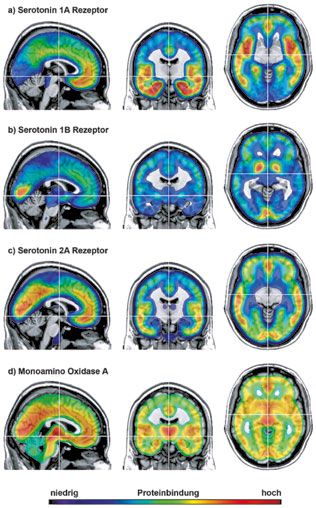

Serotonin gibt uns das Gefühl der Gelassenheit, Ausgeglichenheit, inneren Ruhe und Zufriedenheit. Unter anderem ist es dadurch auch an unserem Appetit und Essverhalten, dem Gefühl der Sättigung und Angstfreiheit beteiligt. Ein

gut genug funktionierendes Serotoninsystem überträgt an seine Serotonin 1A-, 1B-, 2A-Rezeptoren und

die Monoamin Oxidase A

gleichsam die Botschaft, dass wir emotional ausgeglichen, gelassen und zufrieden sind. Das Enzym Monoamin Oxidase A baut

abschließend überschüssiges Serotonin in und an den Synapsen ab.

Die folgende Grafik zeigt funktionelle Magnetresonanz-Tomographie Aufnahmen von Hirnregionen, in denen Ser1A-Rezeptoren,

Ser1B-Rezeptoren, Ser2A-Rezeptoren und MAO A Enzyme am häufigsten lokalisiert wurden:

Copyright � 2016 by J Neurol Neurochir Psychiatr, Heft 1, 2016, S. 18.